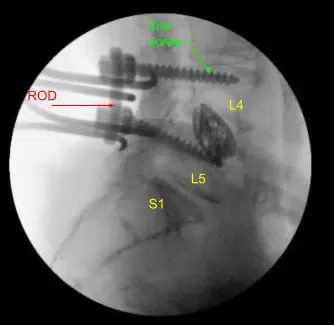

Dada la preocupación por el implante en posición prona y la sensación de que las placas terminales podrían haberse fracturado más, expusimos los procesos transversales de L4 y L5 y usamos el taladro para crear agujeros piloto en el pedículo del lado izquierdo en L4 y L5. Bajo fluoroscopia, guiamos las sondas a través de los pedículos y tocamos cada pedículo, luego colocamos tornillos pediculares en L4 y L5.

Estos tornillos se estimulaban y se comprobaban mediante fluoroscopia, luego se colocaba una roda y se apretaban finalmente los tornillos de tapa. En el lado derecho e izquierdo, decoricamos las facetas y procesos transversales y colocamos nuestra masa de fusión para la artrodesis.